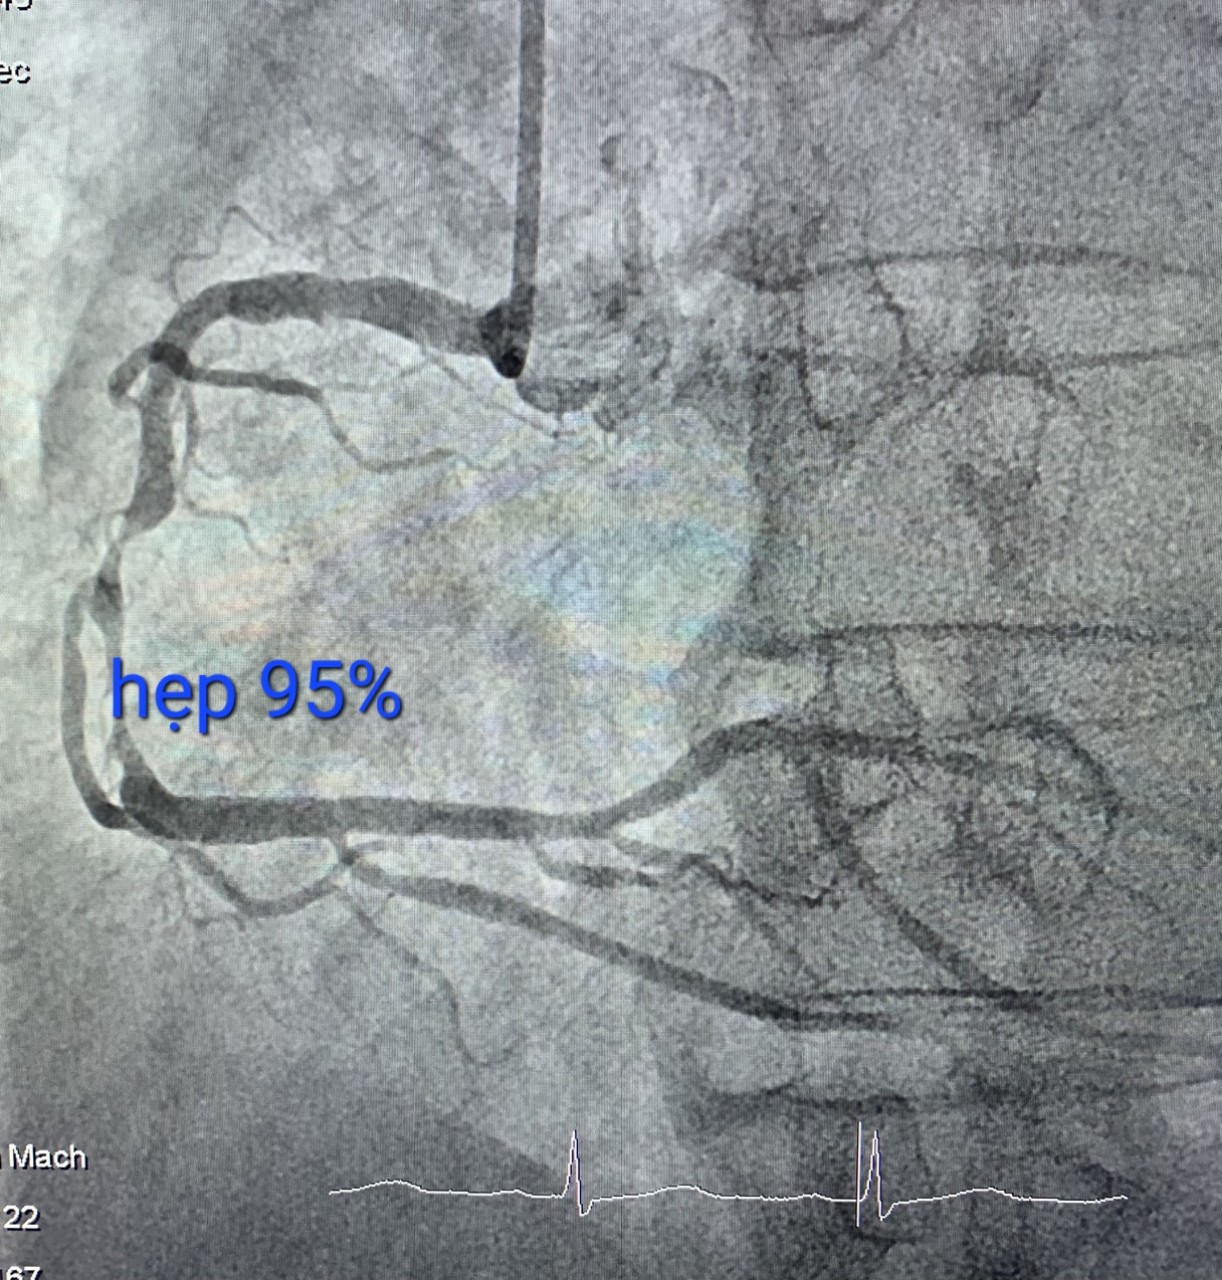

Gần đây, bệnh nhân cảm giác đau giữa xương ức kiểu bóp nghẹt kèm tê nhẹ hàm. Bệnh nhân sau đó đi khám được các bác sĩ chuyên khoa tim mạch chẩn đoán đau ngực do bệnh lý mạch vành và được chỉ định nhập viện chụp mạch vành. Kết quả sau chụp mạch vành cho thấy bệnh nhân bị hẹp 95% động mạch vành phải. Sau khi được các bác sĩ can thiệp đặt stent vành phải các triệu chứng đau ngực của bệnh nhân đã cải thiện rõ rệt.

Hình ảnh trước can thiệp và sau can thiệp. Ảnh BS cung cấp